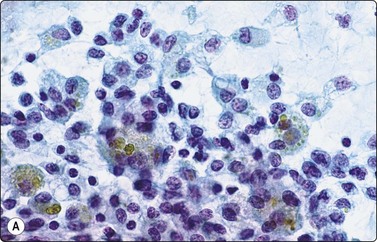

image image image

Fig. 6.28 Poorly differentiated carcinoma

(A,B) Smears showing syncytial clusters of crowded small cells with hyperchromatic nuclei (A, MGG, HP; B, Pap, HP); (C) Tissue section, same case. (H&E, IP).

Smears in poorly differentiated thyroid carcinomas are hypercellular with single cells as well as cells in solid, trabecular and insular patterns. There is marked crowding of cells and tumor cells show high nuclear cytoplasmic ratios (Fig. 6.28).158